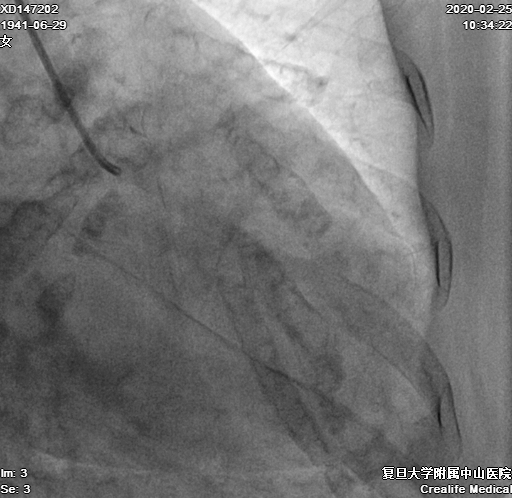

患者右冠异常开口于左冠窦,经左侧桡动脉先后尝试置入7F SAL 0.75SH、1.0SH、EBU 3.5SH、BL 3.25指引导管均无法到达右冠口,最终BL 3.0指引导管成功送至右冠口(图4)

图4